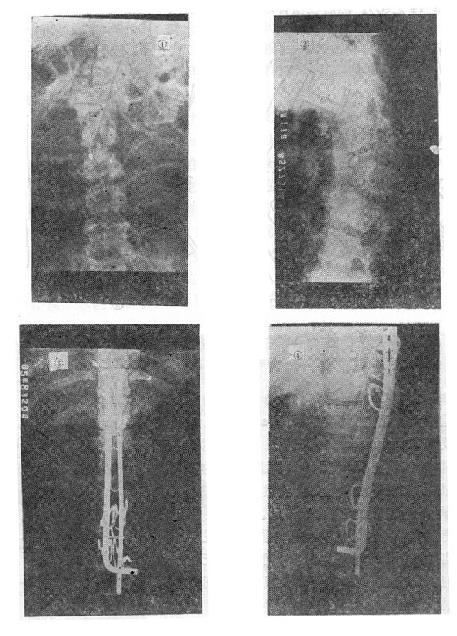

图73-12 垫枕背伸锻炼获良好结果 ①骨折初时;②背伸锻炼3个月后 (二)旋转型脊柱骨折的治疗 用Harrington棍法,不能矫正旋转,最好用Luque棍或Dick法进行矫正与固定。两根“L”型金属棍,放在棘突基底两侧,用每一个椎板下穿过的Luque钢丝固定到骨折部位上、下方各三个椎体椎板上,通过弯好弧度的Luque棍的杠杆作用和拧紧Luque钢丝所产生的矫正力,可以矫正旋畸形,并牢固固定骨折。如不合并神经系统症状,1周后即可下地活动。 (三)爆裂型骨折的治疗 如不合并严重的神经系统症状,损伤又在两周以内者,可以用双Harrington法,撑开矫正,或用Dick手术;可以获得满意的结果(图73-13)。复位后需融合相邻两个椎间隙,因为CT常显示在爆裂型骨折中,相邻的上、下两个椎间盘均有损伤,如不融合,日后取棍后会出现腰痛。使用本法时,如前纵韧带完整,则很容易恢复椎体前方的高度。但爆裂型骨折存在下述三种情况时,需行前路减压术:①合并神经系统症状较重者;②就诊较晚,已两周以上者(常常10天以上就复位比较困难);③脊柱CT扫描显示已有较大的骨折片突出椎管内,使髓腔管变窄超过30%以上者,预示后纵韧带已有明显损伤,使用后路手术方法已无法使骨折片复位。Kostuik复习了日本和多伦多治疗脊柱骨折的结果后证实,前路减压术能使膀胱、肛门及肢体功能得到更好的恢复。

图73-13 爆裂型骨折的治疗 ①术前,骨折脱位;②术后,侧位;③术后,正位 前路手术方法为病人取侧卧位,腰椎骨折由肾切口进入,胸腰段骨折则经切除第10肋之胸腹联合切口进入,结扎节段血管后,切开并向侧方推开椎前胸膜壁层,从腰椎侧方向椎体前方剥离骨膜,先掀起骨膜再进行骨折的处理,有助于防止血管损伤。然后切除骨折处的椎间盘,此时先找出椎间孔前缘,保护好神经和脊髓,再用咬骨钳咬除病椎骨质(保留作植骨用),靠后部分可用电钻磨(图73-14之①②)。对于旋入椎管腔内的骨片,可用刮匙将骨片旋转回原来的部位,减除脊髓的压迫(图73-14之③)。直至看到对侧硬脊膜,然后进行植骨。取一段腓骨嵌入植骨,在一助手将脊柱由后向前推顶的同时,将腓骨卡入,恢复椎体前缘高度(图73-14之④)。然后在植骨块的两侧再植入一些松质骨。

图73-15 椎体后部Chance骨折的治疗 (五)切片状骨折的治疗 因为这种骨折伴有整个韧带的完全撕裂,且常合并截瘫,用Harrington撑开棍治疗后方间隙反而会明显增宽。应选用强度较好的Luque或Dick装置为好,不仅能获得满意的复位(图73-16①~③),而且固定牢固,术后即可随意翻动病人,术后1-2即可让病人起床坐轮椅活动,有利于截瘫病人的康复与护理。